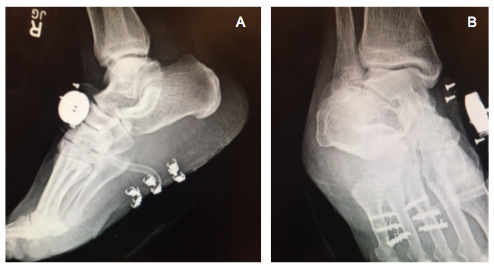

Figure 5 Postoperative medial oblique (A) and lateral (B) radiographic views demonstrating absence of the mass with DermaClose® apparatus in place.

A bulky dressing with a posterior splint was applied to the surgical site and strict non-weight bearing instructions were given. The patient followed up in our wound care clinic after 1 week, at which time the wound was diminished in size to 8.4cm x 0.1cm. The patient continued to follow up once weekly as the wound continued to diminish in size. The device was de-tensioned and removed under posterior tibial nerve block after 3 weeks. At this time, the patient was also allowed to begin protected weight bearing in a fracture boot. At approximately 8 weeks post -op, the wound had healed satisfactorily and the patient was cleared to ambulate in a sneaker. The patient continued to follow up with us over the next 5 months without any residual symptomatology (Figures 3-8).